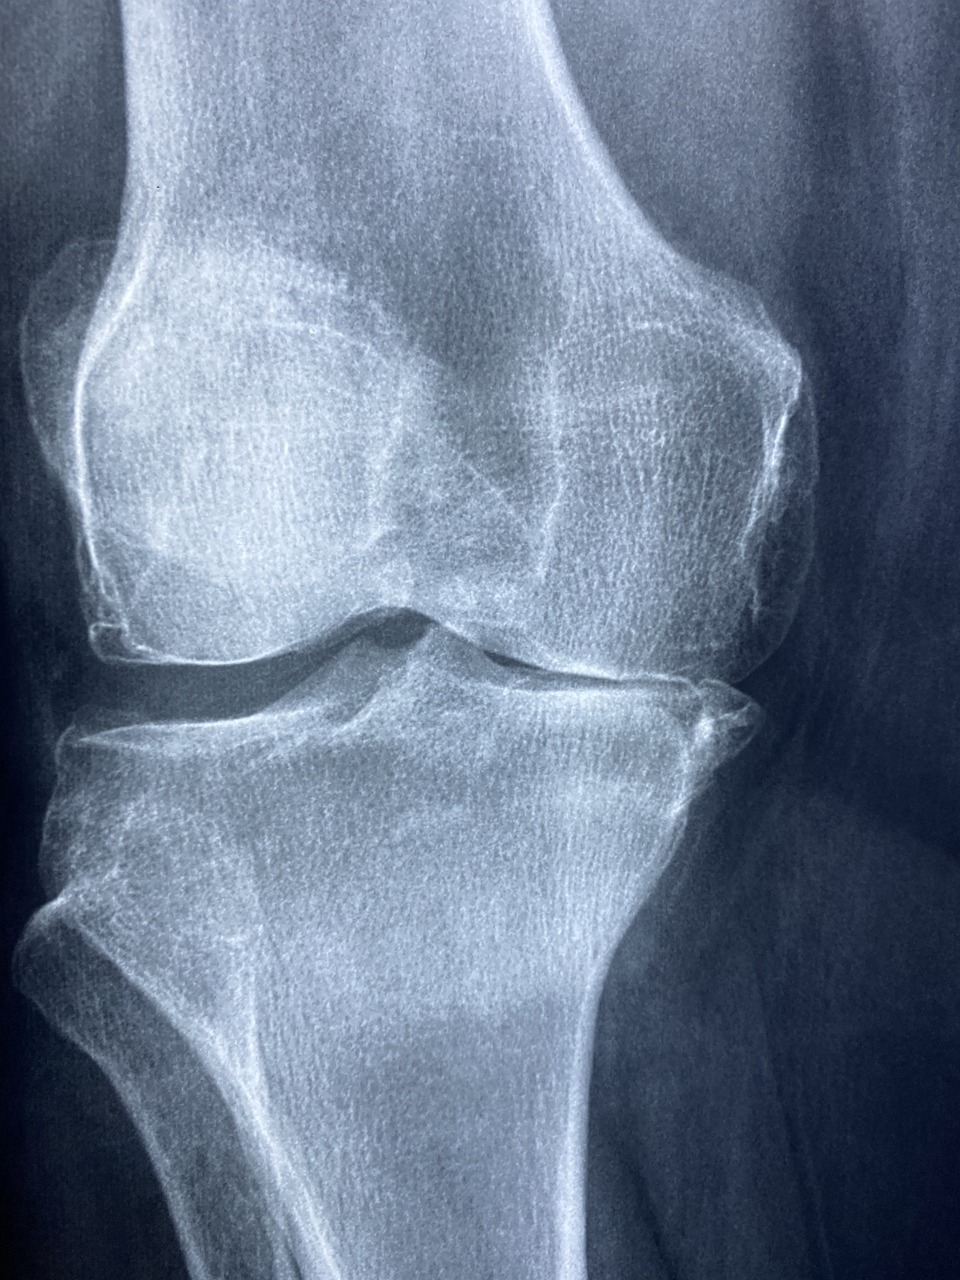

반월상 연골 파열은 무릎 통증의 주요 원인 중 하나로, 스포츠 활동이나 일상생활 중 갑작스러운 움직임으로 인해 발생할 수 있는 대표적인 무릎 부상입니다. 특히 중장년층과 운동선수에게 빈번히 나타나며, 올바른 대처와 재활 없이 방치할 경우 퇴행성 관절염으로 발전할 수 있어 주의가 필요합니다. 본 글에서는 반월상 연골 파열의 수술 여부 결정 기준, 효과적인 재활법, 그리고 일상에서 실천할 수 있는 통증 관리법에 대해 자세히 알아보겠습니다.

반월상 연골은 무릎 관절의 안정성과 충격 완화를 담당하는 중요한 조직입니다. 이 연골이 파열될 경우 통증, 부종, 무릎 잠김 현상 등이 나타날 수 있습니다. 그러나 모든 파열이 수술로 이어지는 것은 아닙니다. 우선 파열의 위치와 형태에 따라 치료 방법이 달라집니다. 혈액 공급이 잘 되는 외측 부분의 파열은 자연 치유 가능성이 높아 비수술적 치료로 회복되는 경우가 많습니다. 반면, 혈류 공급이 적은 내측 파열은 회복이 어려워 수술이 필요한 경우가 많습니다. 비수술 치료는 안정, 냉찜질, 압박, 고정(Rest, Ice, Compression, Elevation - RICE 요법), 물리치료 등이 포함됩니다. 또한 통증 완화와 회복을 돕는 약물치료와 재활 운동이 병행됩니다. 수술이 필요한 경우는 다음과 같습니다: - 연골 조각이 관절 안에 끼여 무릎이 잠기는 경우 - 3개월 이상 비수술 치료에도 증상이 지속될 경우 - 활동량이 많은 운동선수나 직업상 무릎 사용이 많은 사람 수술은 관절경을 통해 시행되며, 절개가 적고 회복이 빠른 편입니다. 다만 수술 후 재활과 운동이 필수이므로 단기적 해결보다는 장기적 회복 전략이 중요합니다.